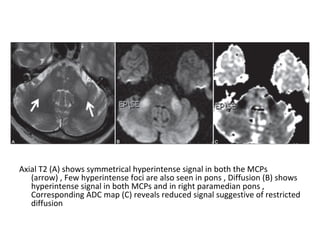

Axial T2 (A) shows symmetrical hyperintense signal in both the MCPs

(arrow) , Few hyperintense foci are also seen in pons , Diffusion (B) shows

hyperintense signal in both MCPs and in right paramedian pons ,

Corresponding ADC map (C) reveals reduced signal suggestive of restricted

diffusion